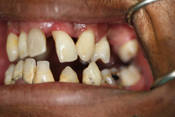

WORST TEETH Pictures from Warren Dentistry

This can happen to your teeth when proper Dental Hygiene is not practiced.

Patient 4